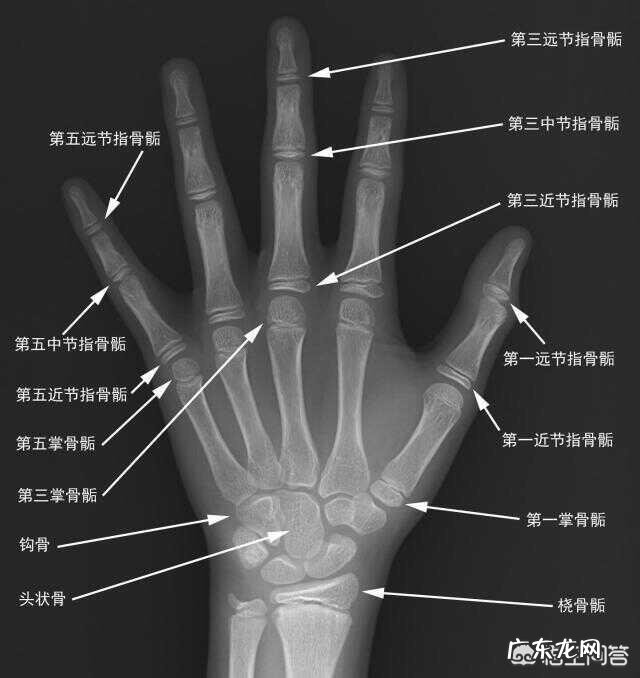

许多家长也会问 , 测骨龄要去省会城市不方便 , 当地没有懂骨龄与性早熟的医生 。我告诉大家一个办法 , 先去任何一家医院 , 不管大小拍摄一张孩子左手手掌骨龄片 , 去淘宝淘一下骨龄检测服务 , 许多专业骨龄医生利用互联网开了店铺 , 服务态度很好 , 可以读片分析咨询建议 , 很方便 。